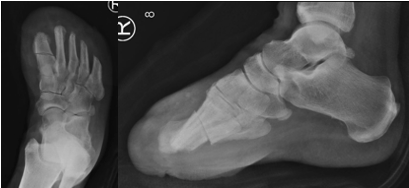

Thus, it is paramount that we treat foot ulcers in an expeditious manner for these patients. This requires podiatrists to work in a multidisciplinary team, making sure there is adequate arterial inflow, infection management, and optimization of any underlying medical conditions. Once this has been established, one should apply orthoplastic techniques to address the soft tissue deficits and correct any underlying musculoskeletal abnormalities with the goal of achieving a fully healed, plantigrade, functional foot.19